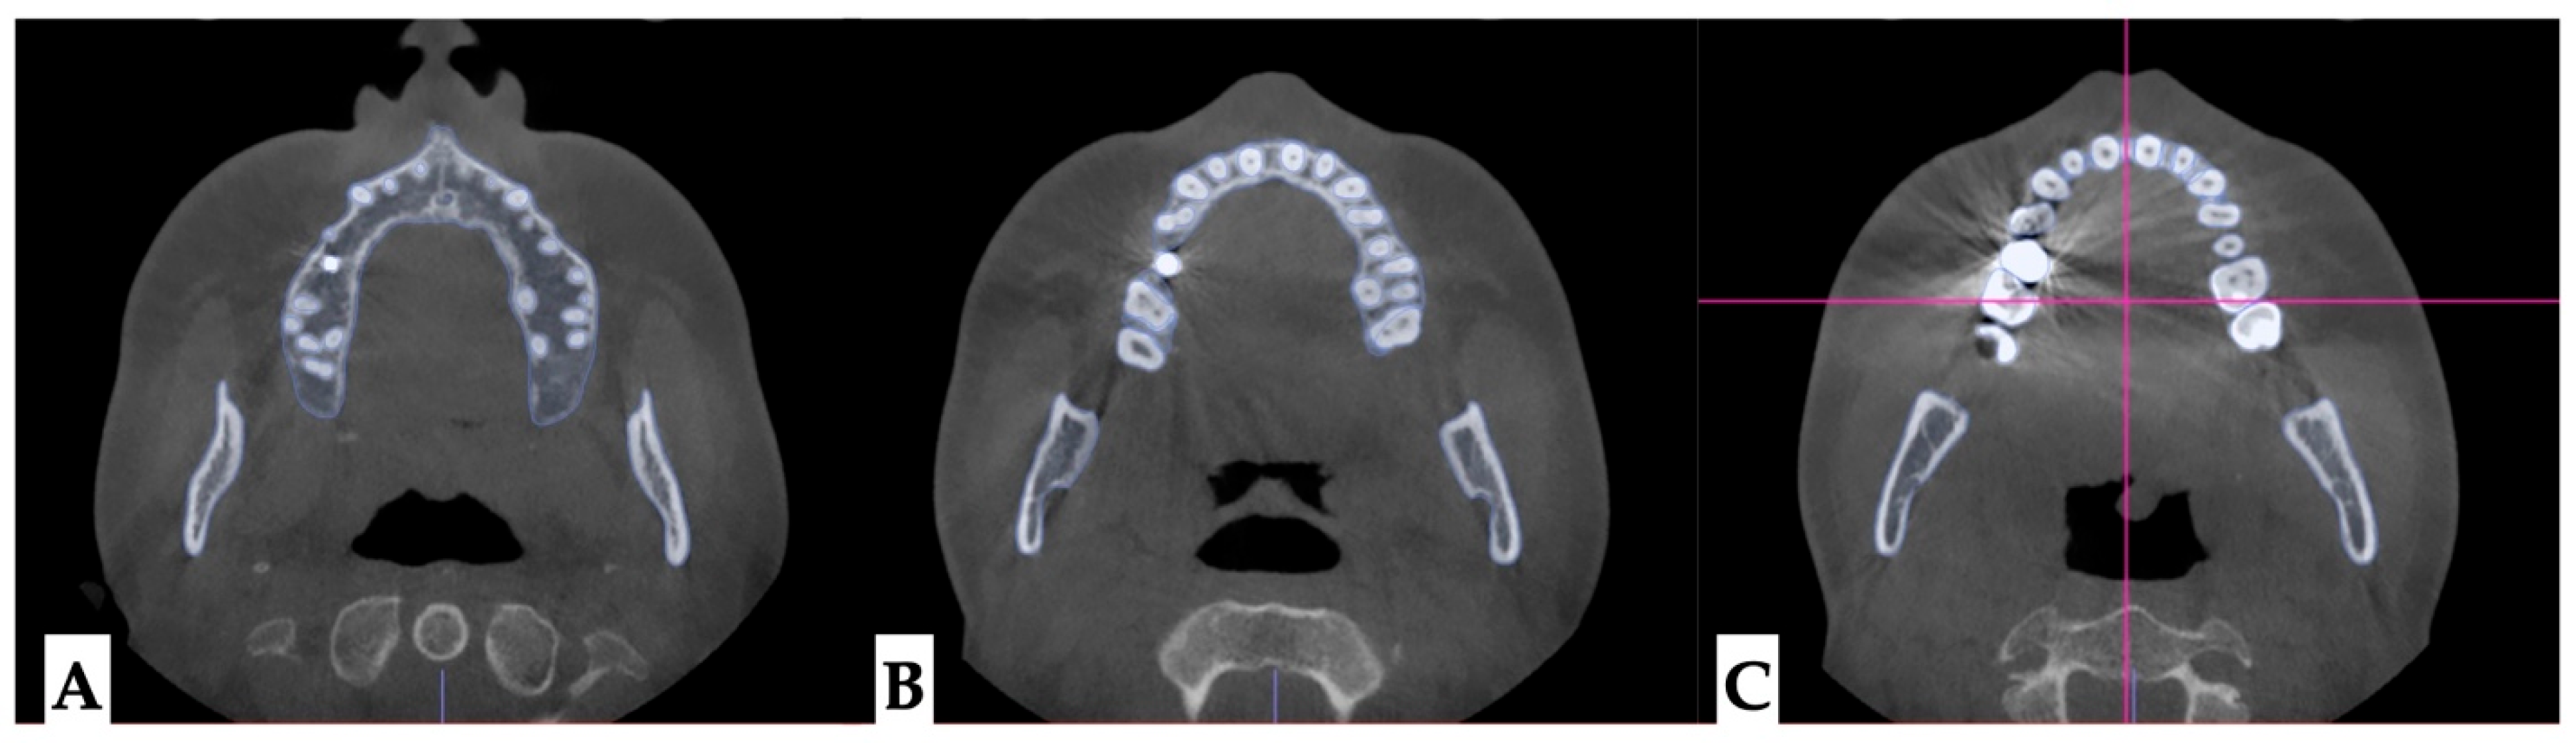

2. Materials and Methods

2.1. Pre-Treatment Records and Analysis

2.2. Pre-Treatment Diagnosis

2.3.1. Surgical Protocol

2.3.2. Design of 3D Surgical Guide

2.3.3. Osteotomy Planning and Appliance Design